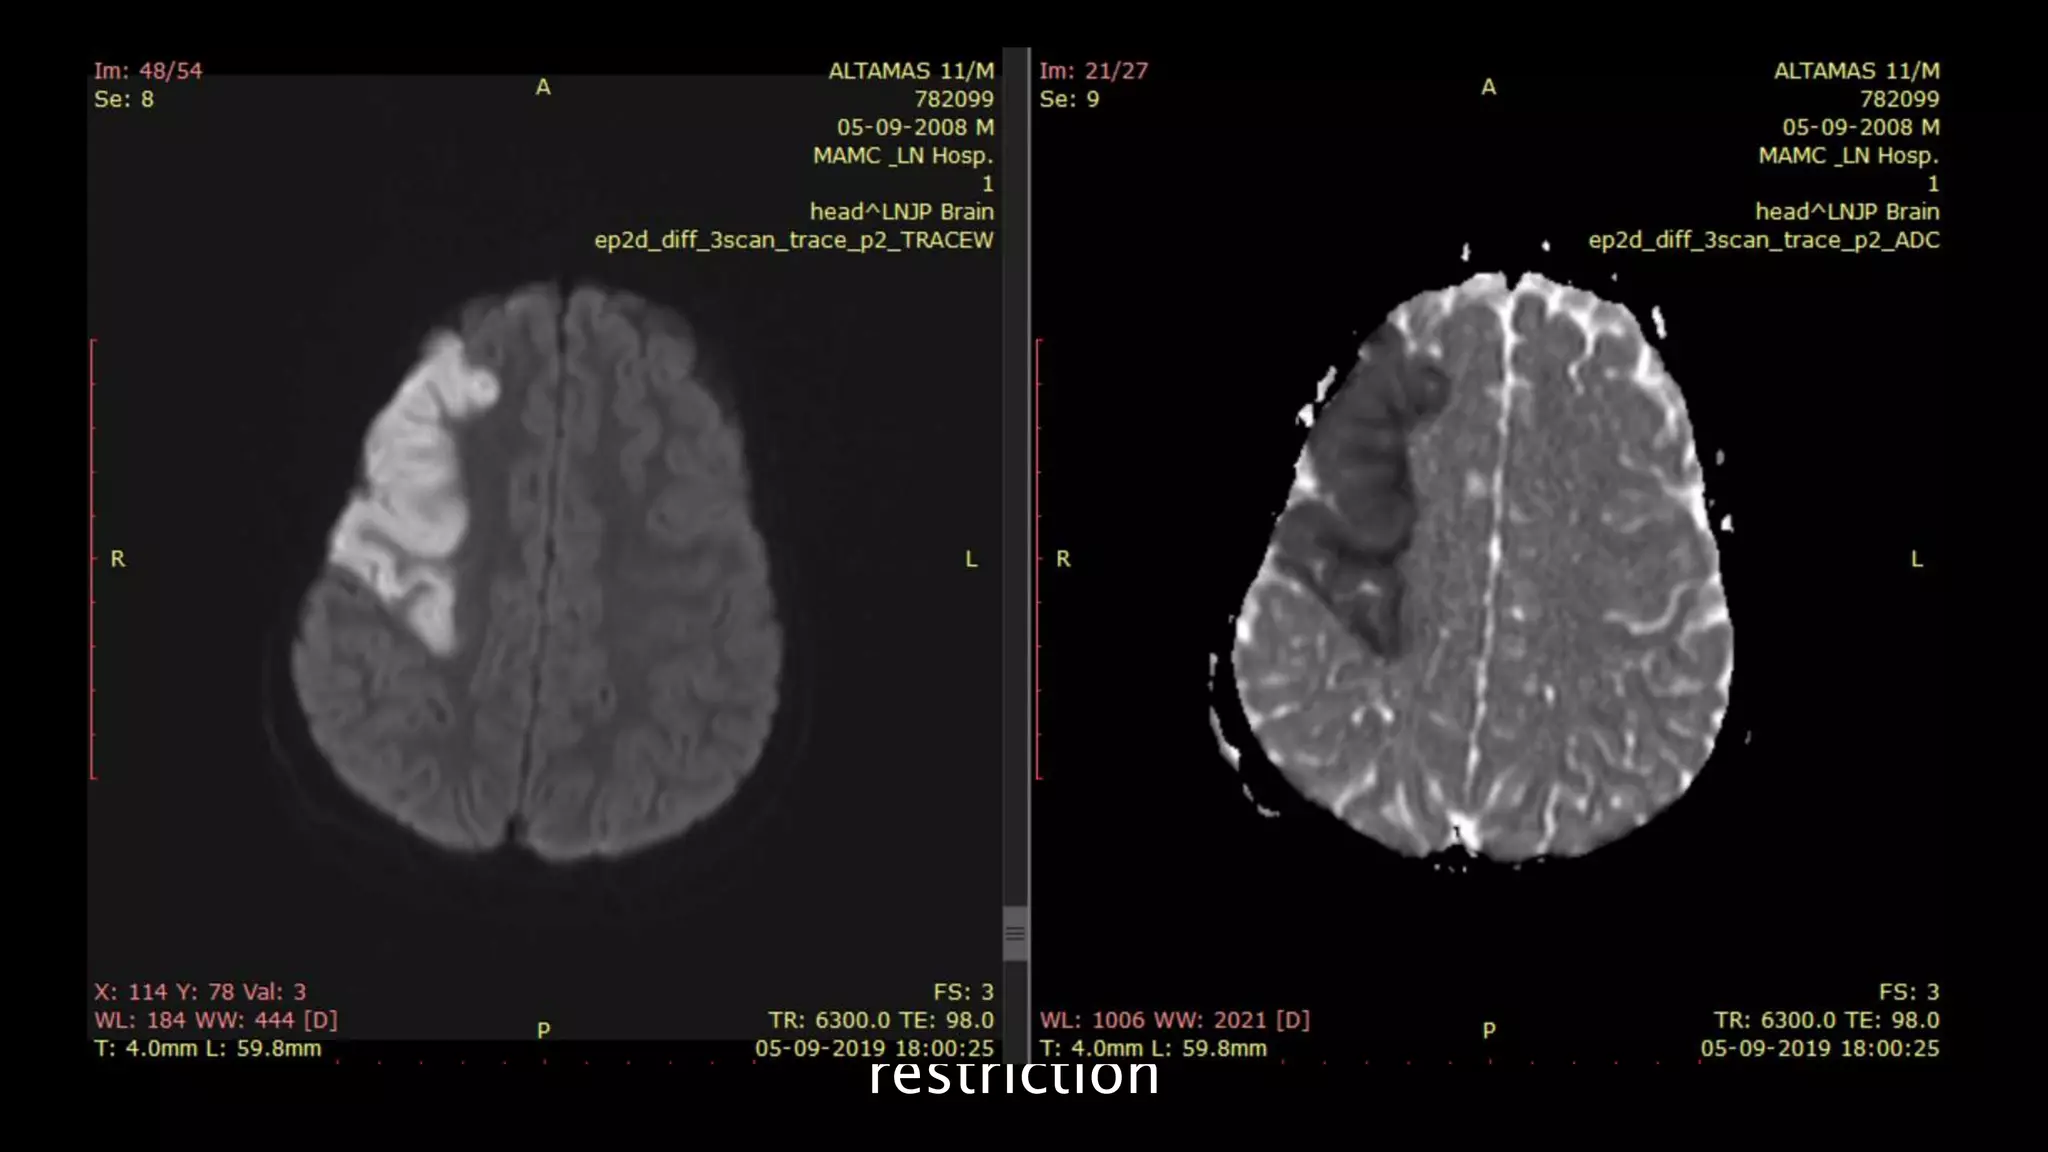

HYPERINTENSE

ON DWI

HYPOINTENSE

ON ADC map

Head of right

caudate

nucleus and

lentiform

nucleus show

diffusion

restriction

• #46 Here is the example of the same patient shown before. DWI shows hyperintensity in the right frontoparietal region with hypointensity on corresponding ADC map s/o diffusion restriction